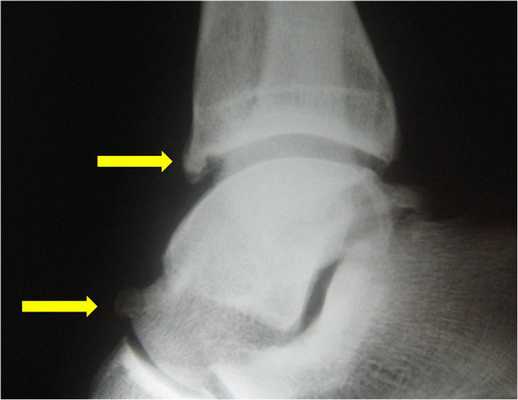

Рентгенограммы пациента с задним импиджмент синдромом

Выполняются рентгенограммы голеностопного сустава в двух проекциях. На обычных рентгенограммах остеофиты (костные шпоры) на голени или таранной кости чётко определяются. Можно выполнить боковые стресс-рентгенограммы, когда при приседании на корточки можно выявить соударение костных поверхностей в передней части голеностопного сустава, а при вставании на носки - соударение в задних структурах голеностопного сустава.

На рентгенограмме нередко можно увидеть гипертрофированный задний отросток таранной кости или os trigonum. В случаях перенесенных ранее травм мы ищем признаки несросшегося перелома в этой области.